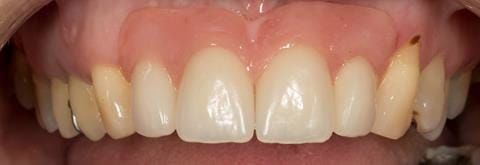

- High smile line showing gum above gingival zeniths of upper front teeth when smiling. Aesthetic failure of the upper four incisors with inflammation of the gingivae and mis-match of the gingival zenith levels.

- Extract the upper 2-2 teeth and replace with an interim acrylic based partial denture. Reline the interim denture over 9 - 12 months, replacing with a definitive cobalt chromium based partial denture. The definitive denture would ideally be designed as an occlusal protective splint to reduce the the potential for mechanical wear and breakages of the moderately/heavily restored maxillary dentition. In addition, should further upper teeth require extraction they could be added on to the denture cobalt chromium framework - therefore a new prosthesis would not be required as future teeth are lost. This option would produce an excellent aesthetic outcome. This is the option the patient chose to have.

Following consultation and second discussion appointment the patient chose to have option 3 namely, a maxillary cobalt chromium based partial denture/protective occlusal splint. The clinical situation and treatment process is shown in detail below with photographs. The patient was successfully rehabilitated with this and her quality of life considerably improved. The clinical work was provided by Finlay and the technical work by Rowan.